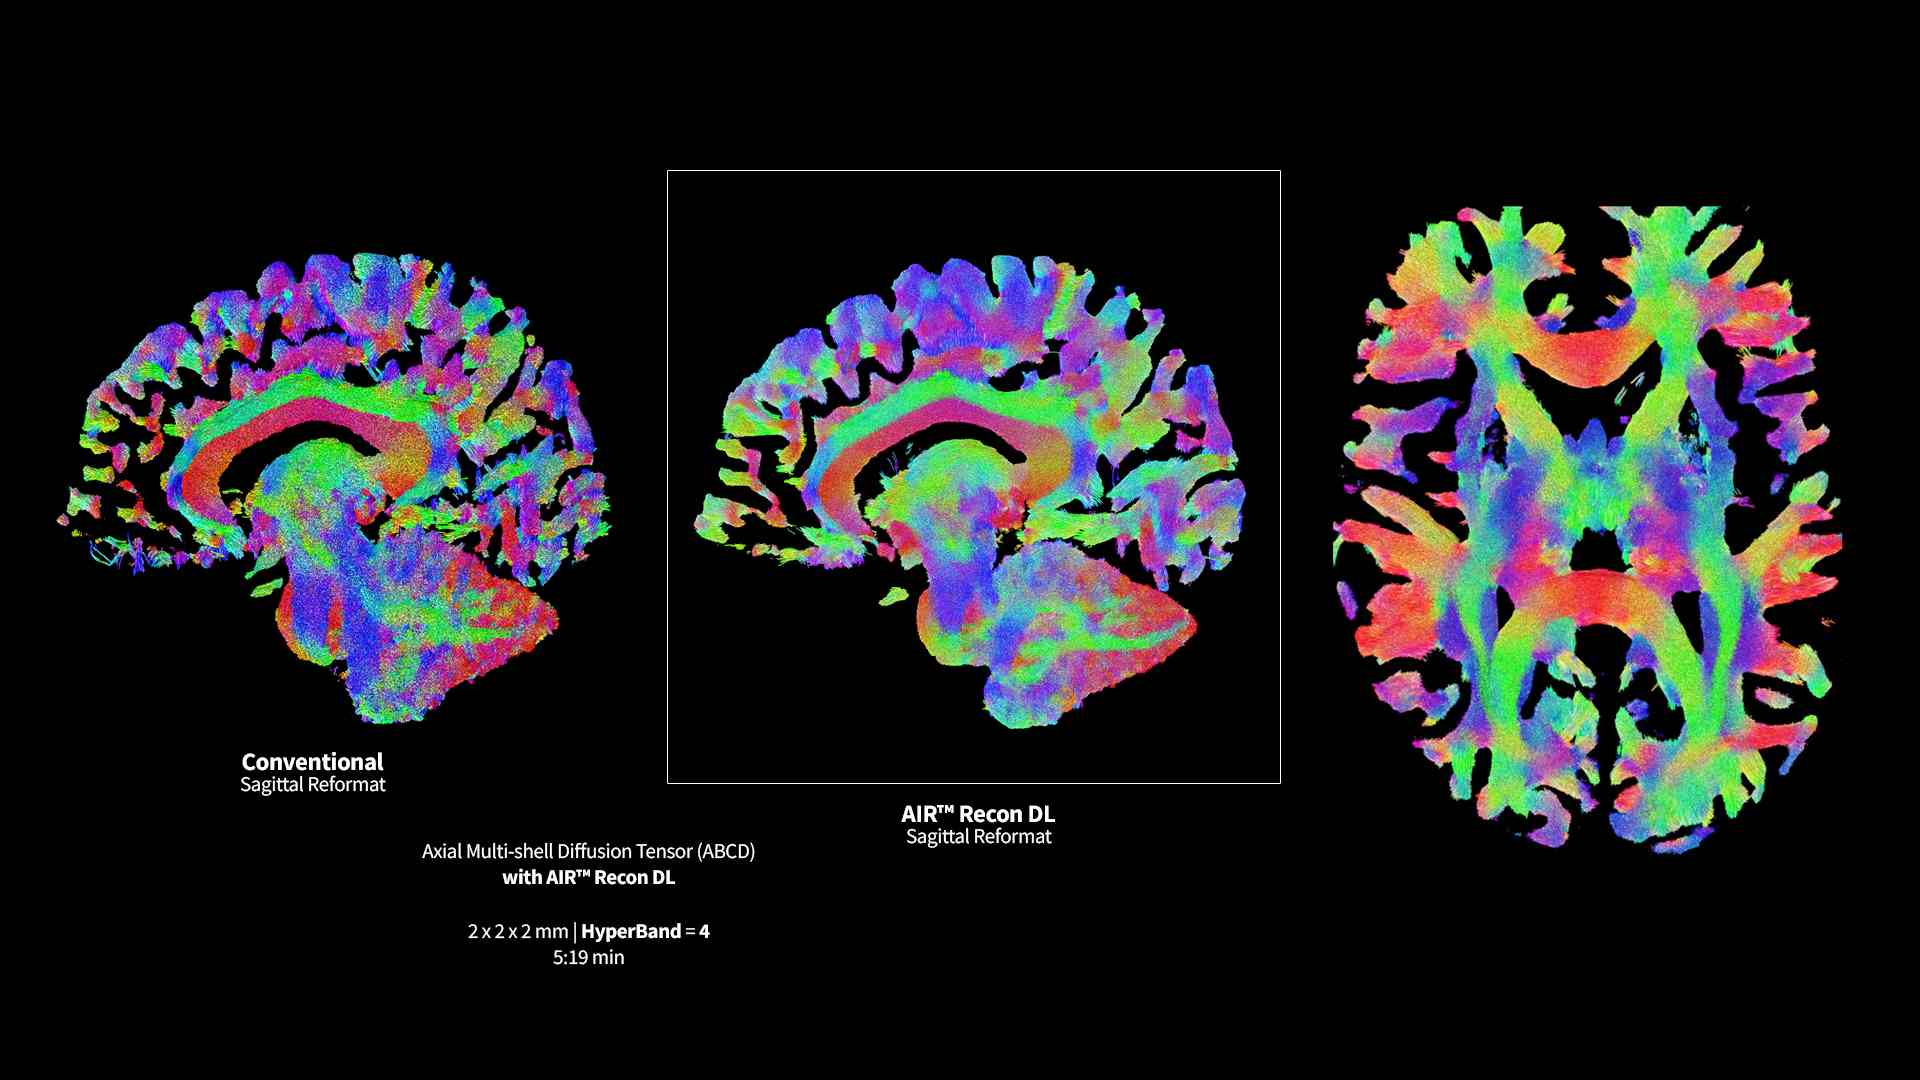

Revolutionary, deep-learning-based reconstruction techniques such as AIR™ Recon DL provide sharper, clearer, and accurate images

Pin-sharp image quality and exceptional speed with AIR™ Recon DL and Sonic™ DL​

Experience pin-sharp precision and remarkable speed with a 3T SIGNA™ Premier MRI scanner, coupled with AIR™ Recon DL and Sonic™ DL.